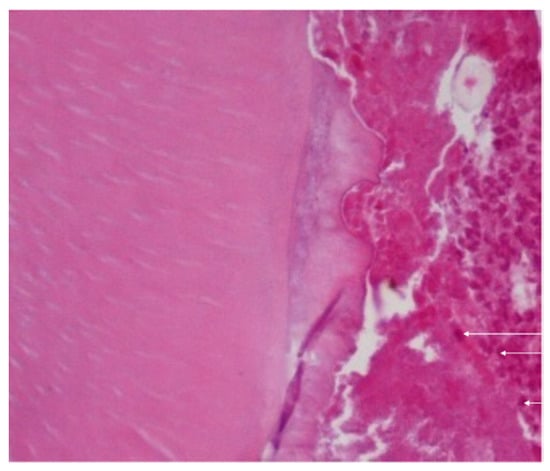

Twenty-one days after the periapical lesion inductions, an increased periodontal ligament with loss of lamina dura and alveolar bone resorption was observed. In addition, the lesion area had considerably enlarged in the saline solution group (190,515 ± 143,55 pixels), whereas in the ZOL group, it was reduced (174,822 ± 14,808 pixels), with statistical differences (p = 0.027) (Figure 2 and Figure 4).

At this time point, histological analysis in all groups also exhibited periapical lesions with enlargement of the periodontal space and disorganization of the periodontal ligaments, with large numbers of macrophages present throughout the periodontal ligament, and no osteonecrosis was observed (Figure 5). In addition, fibres and blood vessels occupied the lost bone space.

Figure 4. (a) Histological analysis exhibited an increased periodontal ligament with loss of lamina dura and alveolar bone resorption was considerably enlarged in the saline-solution group (190,515 ± 14,355 pixels). Magnification: 40×. (b) Histologic analysis exhibited an increased periodontal ligament with loss of lamina dura and alveolar bone resorption which was reduced in the ZOL group.

Figure 5. Histological analysis in all groups also exhibited periapical lesions with enlargement of the periodontal space and disorganization of the periodontal ligaments, with large number of macrophages present throughout the periodontal ligament (arrow), and no osteonecrosis was observed. Magnification: 400×.